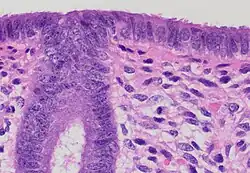

Structure

The endometrium consists of a single layer of columnar epithelium plus the stroma on which it rests. The stroma is a layer of connective tissue that varies in thickness according to hormonal influences. In the uterus, simple tubular glands reach from the endometrial surface through to the base of the stroma, which also carries a rich blood supply provided by the spiral arteries. In women of reproductive age, two layers of endometrium can be distinguished. These two layers occur only in the endometrium lining the cavity of the uterus, and not in the lining of the fallopian tubes where a potentially life-threatening ectopic pregnancy may occur nearby.[4][5]

- The functional layer is adjacent to the uterine cavity. This layer is built up after the end of menstruation during the first part of the previous menstrual cycle. Proliferation is induced by estrogen (follicular phase of menstrual cycle), and later changes in this layer are engendered by progesterone from the corpus luteum (luteal phase). It is adapted to provide an optimum environment for the implantation and growth of the embryo. This layer is completely shed during menstruation.

- The basal layer, adjacent to the myometrium and below the functional layer, is not shed at any time during the menstrual cycle. It contains stem cells that regenerate the functional layer,[1] which develops on top of it.

It is possible to identify the phase of the menstrual cycle by reference to either the ovarian cycle or the uterine cycle by observing microscopic differences at each phase—for example in the ovarian cycle:

| Phase | Days | Thickness | Epithelium |

|---|---|---|---|

| Menstrual phase | 1–5 | Thin | Absent |

| Follicular phase | 5–14 | Intermediate | Columnar |

| Luteal phase | 15–27 | Thick | Columnar. Also visible are arcuate vessels of uterus |

| Ischemic phase | 27–28 | Columnar. Also visible are arcuate vessels of uterus |